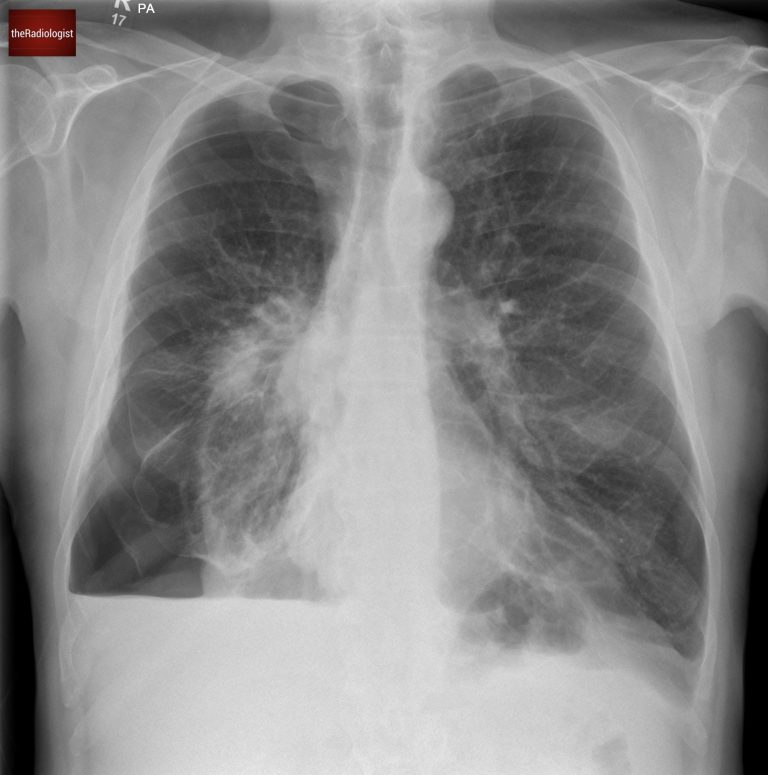

A man in his 50s arrives at the Emergency Department with sudden breathlessness, following a few weeks of a productive cough. A chest X-ray is performed, can you spot the diagnosis?

PA view of a chest X-Ray of a male in his 50s

Here we have a PA chest X-ray with a lot going on. Did you notice the right-sided pneumothorax?

Going back to our case you will see a clear pleural line at the right lung apex whilst there is also a component at the right lung base, which is less commonly seen.

Did you spot the white pleural line both at the apex and within the right lower zone?

We can also see an air-fluid level at the right lung base – this represents a ‘hydropneumothorax’ ie there is both fluid and gas within the pleural space. Note how this appears slightly different to a standard pleural effusion where you get a ‘meniscus sign’ rather than a straight air-fluid level – this is because there is no surface tension from air in a hydropneuomothorax.

With a hydropneumothorax given the lack of surface tension we commonly see an air-fluid level rather than a meniscus sign that we see with a pleural effusion.

Now if we look at our case we can see the trachea and mediastinum are central meaning there is no tension pneumothorax.

In our case the trachea is in a normal position with no signs of shift to suggest shift in the context of tension. Note minor deviation of the trachea to the right at the level of the aortic arch is normal.

There isn’t just a pneumothorax in this case, the underlying lung looks abnormal. Looking closely we can see a right mid zone opacity and a second opacity behind the right hilum (see the image below).

Look closely and you will find two opacities within the right mid zone, one within the right mid zone and another overlying the right hilum.